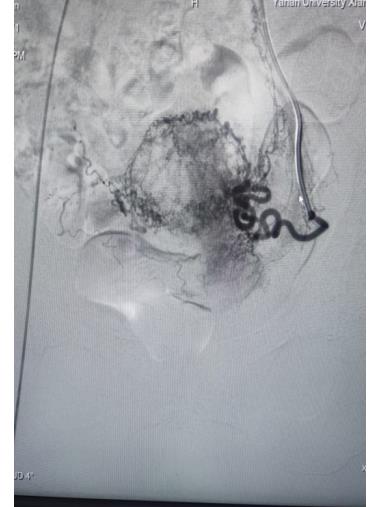

子宮動(dòng)脈栓塞術(shù)屬于血管介入性治療,方法是于股動(dòng)脈穿刺進(jìn)針插入導(dǎo)管,在X射線造影下定位進(jìn)入兩側(cè)子宮動(dòng)脈,注入栓塞劑完全栓塞子宮動(dòng)脈,從而達(dá)到止血或讓子宮肌瘤和病灶缺血壞死的目的;2022年12月6日,在崔旭輝主任、孟慶槐副主任醫(yī)師、馬力主治醫(yī)師等我院介入團(tuán)隊(duì)協(xié)作下,成功為患者進(jìn)行了雙側(cè)子宮動(dòng)脈栓塞術(shù),術(shù)后患者子宮異常出血停止,效果立竿見影,患者病情恢復(fù)良好。

左側(cè)子宮動(dòng)脈栓塞前后對(duì)照